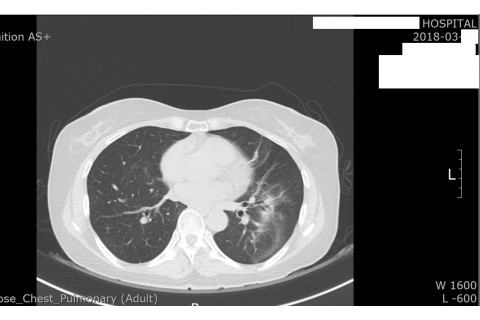

숨케어한의원에서는 전화예약을 받고 있습니다. 내원시 엑스레이, CT사진, 폐기능검사지를 가지고 오시면 자세한 상담이 가능합니다.